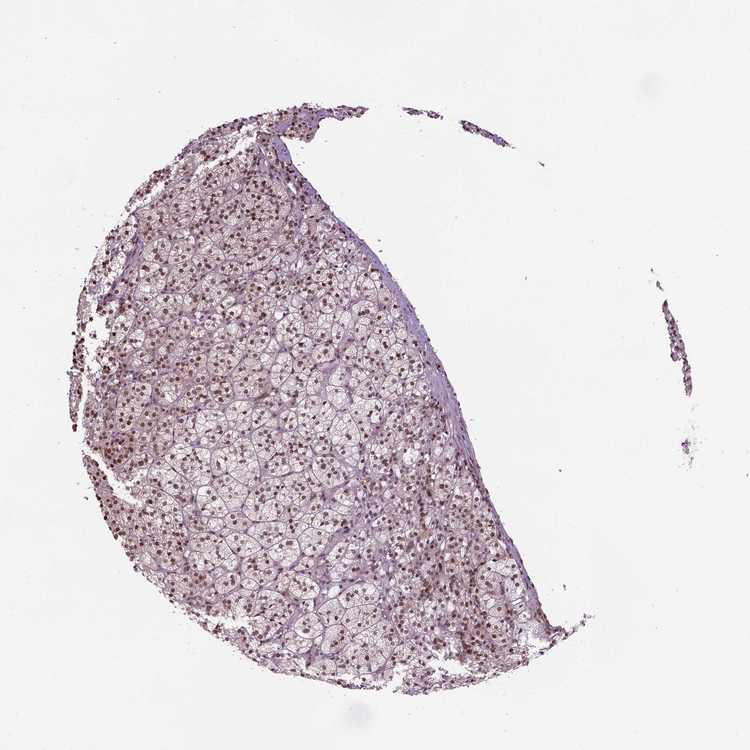

ADRENAL GLAND - Antibody stainingi

Antibody staining in the annotated cell types in the current human tissue is reported as not detected, low, medium, or high, based on conventional immunohistochemistry profiling in selected tissues. This score is based on the combination of the staining intensity and fraction of stained cells.

Each image is clickable and will lead to virtual microscopy that enables deeper exploration of all samples and also displays staining intensity scores, fraction scores and subcellular localization as well as patient and tissue information for each sample.

Antibody HPA069497Antibody CAB002786Antibody CAB069881

Glandular cells LowHighMedium